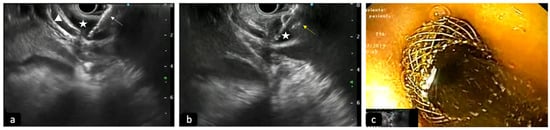

Figure 3.

Deployment of LAMS into a dilated common bile duct (CBD) to perform EUS-guided biliary drainage. (a) Cystotome of LAMS (white arrow) conducted into the CBD (star) under EUS-guide; triangle: cystic duct. (b) EUS view of the opening of the distal flange of LAMS (yellow arrow) into the CBD (star). (c) Luminal view of proximal flange opened with bile outflow.

In patients with biliary obstruction, ERCP has always been considered the initial therapeutic approach, with a success rate between 90 and 97% of cases; however, in some situations, such as post-surgical anatomic abnormality, difficult cannulations or inaccessible papillas, it can be ineffective []. In similar scenarios, EUS-guided access to the BD is becoming a viable and widely used alternative to classic trans-papillary access (Figure 3). EUS-BD can provide the drainage of both intra- and extra-hepatic ducts, bypassing the stenotic papilla and maintaining an endoscopic, minimally invasive approach. EUS-BD also competes with percutaneous biliary drainage (PTBD), avoiding the need for an external catheter and the related discomfort for patients and possible complications, such as infections, bleeding, dislocation or bile leak. Therefore, according to ESGE guidelines, in the event of ERCP failure, EUS-BD should be preferred instead of PTBD [].